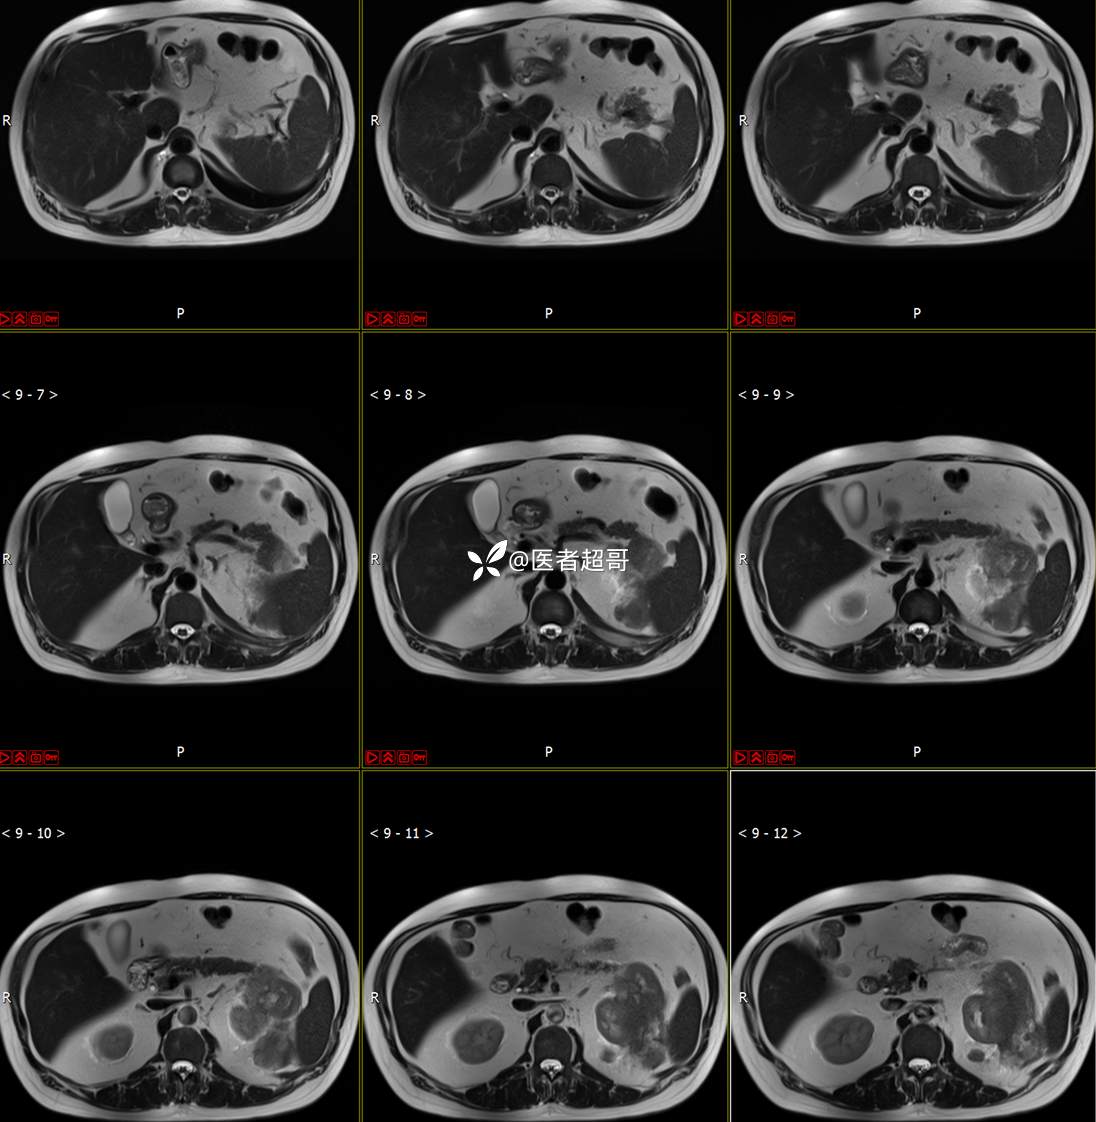

主 诉:查体发现左肾肿物9天。

现病史:患者9天前于附属医院行常规腹部CT检查时,发现左肾占位性病变并肾周脂间隙软组织增多,自述无明显腰腹部不适,无尿频、尿急、尿痛及肉眼血尿,未予特殊治疗,患者近期无头晕头迷,胸闷气急,腹胀腹泻及其他部位明显不适,遂至我院就诊,门诊以“肾肿物”收入院,患者自发病以来,精神可,睡眠饮食可,大便正常,体重无明显减轻。